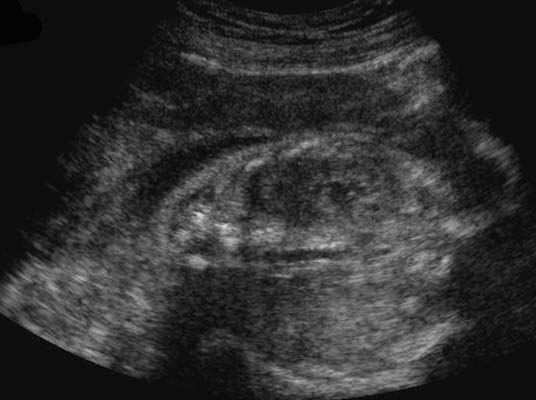

Sur une coupe transversale, deux lacunes de part et d’autre du rachis. Image obtenue plus tardivement en coupe longitudinale (17 – 18 SA).

En coupe longitudinale (de dehors en dedans), aspect en haricot :

*Capsule rénale : fine mais très échogène, permet de suivre le contour du rein.

*Parenchyme rénal : peu échogène, épais de 8 à 10 mm en fin de grossesse. On dissocie la médullaire ou les pyramides sont presque vides d’écho sans liseré et la corticale plus échogène représentée par de fins échos denses et homogènes